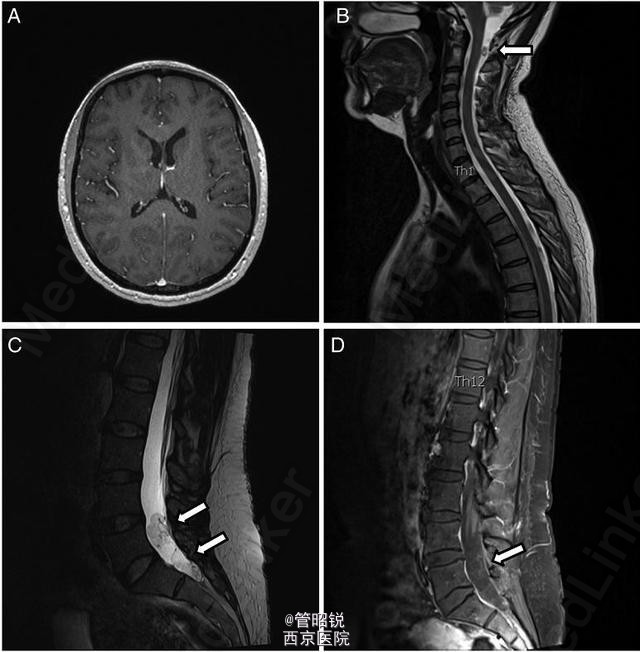

头颅 MRI 未见明显异常(图 1A)。脑脊液结果示:中性粒细胞 133 个 /μl,嗜酸性粒细胞 38%。血清囊虫抗体滴度 106(正常≤0)。脊髓 MRI 示:颈部单发囊性占位,腰部蛛网膜下腔多发囊性占位(图 1B-D)

诊断为脊髓囊虫病,给予阿苯达唑 (2×400 mg/ 天) 驱虫、激素(强的松 60 mg/ 天)抗炎治疗 4 周。治疗期间,患者症状明显缓解。

随访 6 个月时,颈部疼痛仍未见缓解,MRI 示颈部囊性占位体积有所增大。建议囊虫患者可反复驱虫治疗(来源于 J Neurol Neurosurg Psychiatry)脑囊虫病是中枢神经系统常见的寄生虫感染性疾病,同时伴脊髓囊虫的发生率仅为 0.25%-5.8%,而单纯脊髓囊虫病十分罕见。脊髓囊虫病的发生是因为脑囊虫病常发生在基底池,基底池内的幼虫可进入脊髓蛛网膜下腔,并靠自身重力向下迁移,直至腰骶部,在此有足够的空间供其生长发育。这就能解释颈部和腰骶部同时出现占位的现象。由此可见,单纯的头颅 MRI 并不能排除患者的脊髓囊虫病